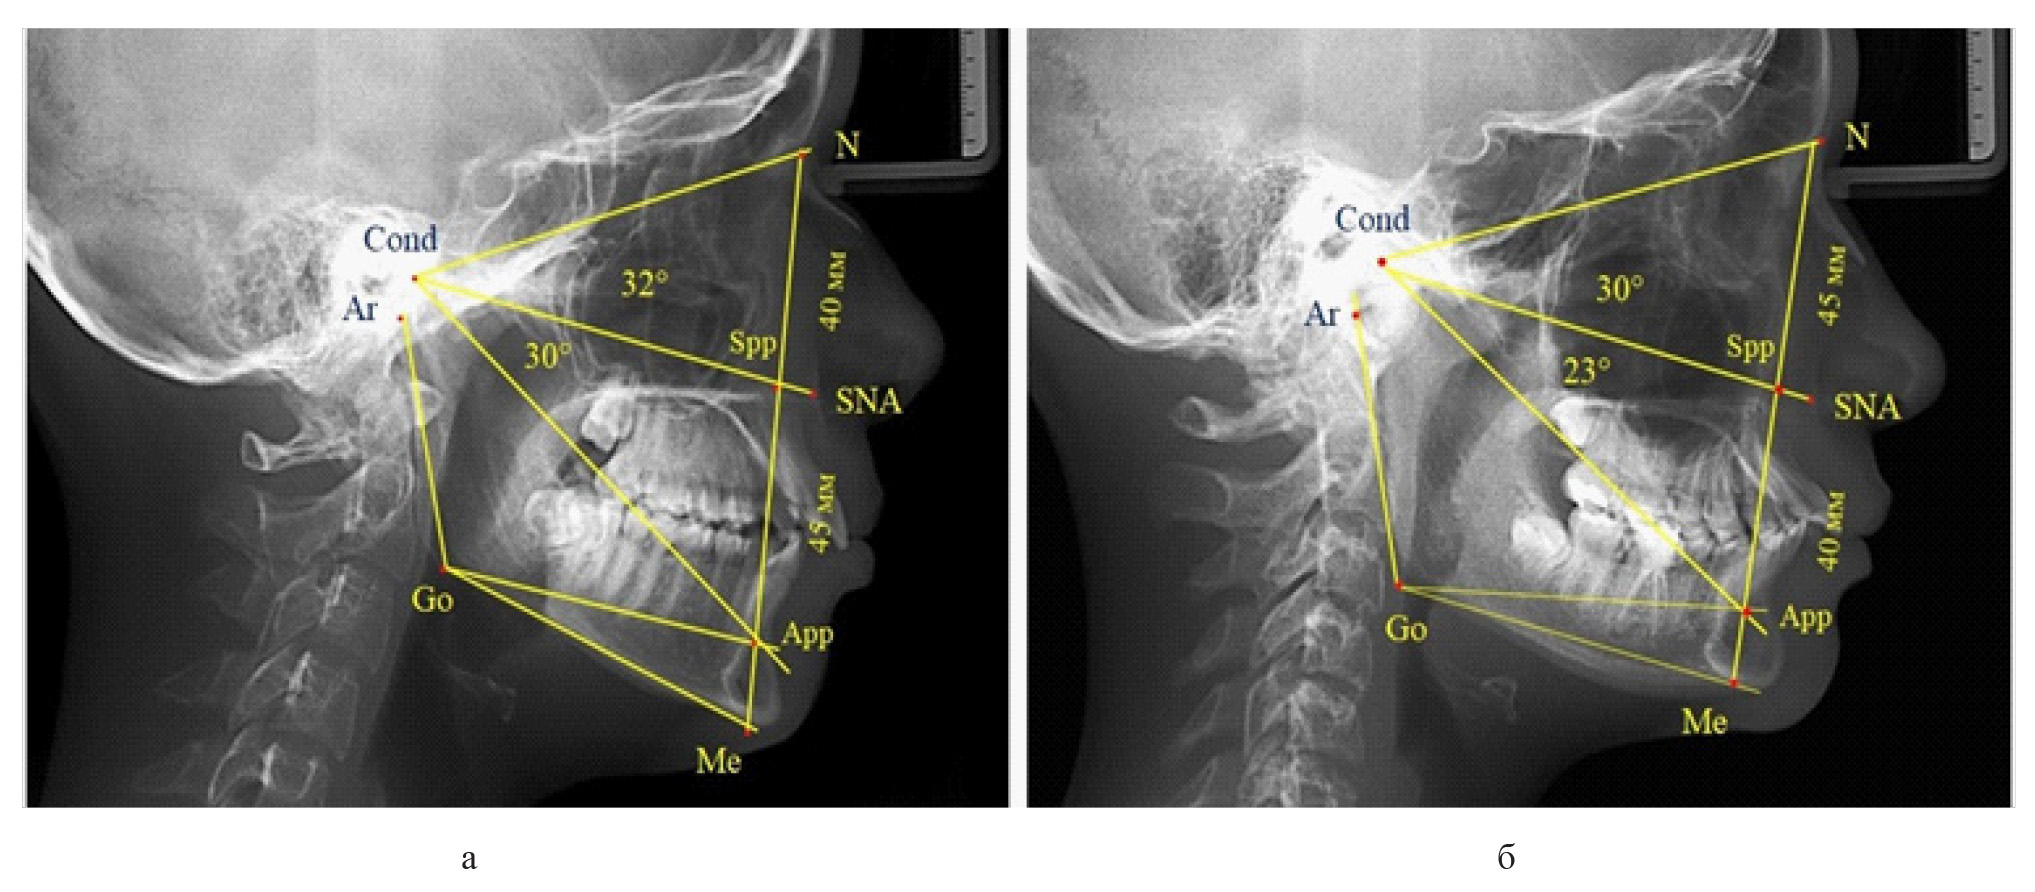

Результаты исследования людей с физиологической окклюзией показали, что у 46 человек [(82,14 ± 5,11) %], параметры назального отдела лица соответствовали оптимальным показателям. При этом у 38 человек [(67,85 ± 6,14) %], определились физиологические показатели параметров гнатической части лица.

У 6 человек [(10,71 ± 4,13) %], отмечалось увеличение параметров гнатической части до уровня физиологического вертикального показателя, а у 2 человек [(3,57 ± 2,48) %], незначительное снижение гнатической части (рис. 3).

Рис. 3. Сравнительный анализ ТРГ с оптимальными размерами носового отдела и оптимальными (а), укороченными физиологическими (б) и увеличенными физиологическими (в) размерами гнатической части лица

Признаки снижения высоты назального отдела вплоть до уровня горизонтального патологического типа при физиологической окклюзии были определены у 10 человек [(17,86 ± 5,11) %]. При этом параметры гнатического отдела соответствовали физиологической норме либо физиологическому горизонтальному типу (рис. 4).

Рис. 4. Варианты ТРГ с укороченными размерами носового отдела и оптимальными (а) и укороченными (б) размерами гнатической части